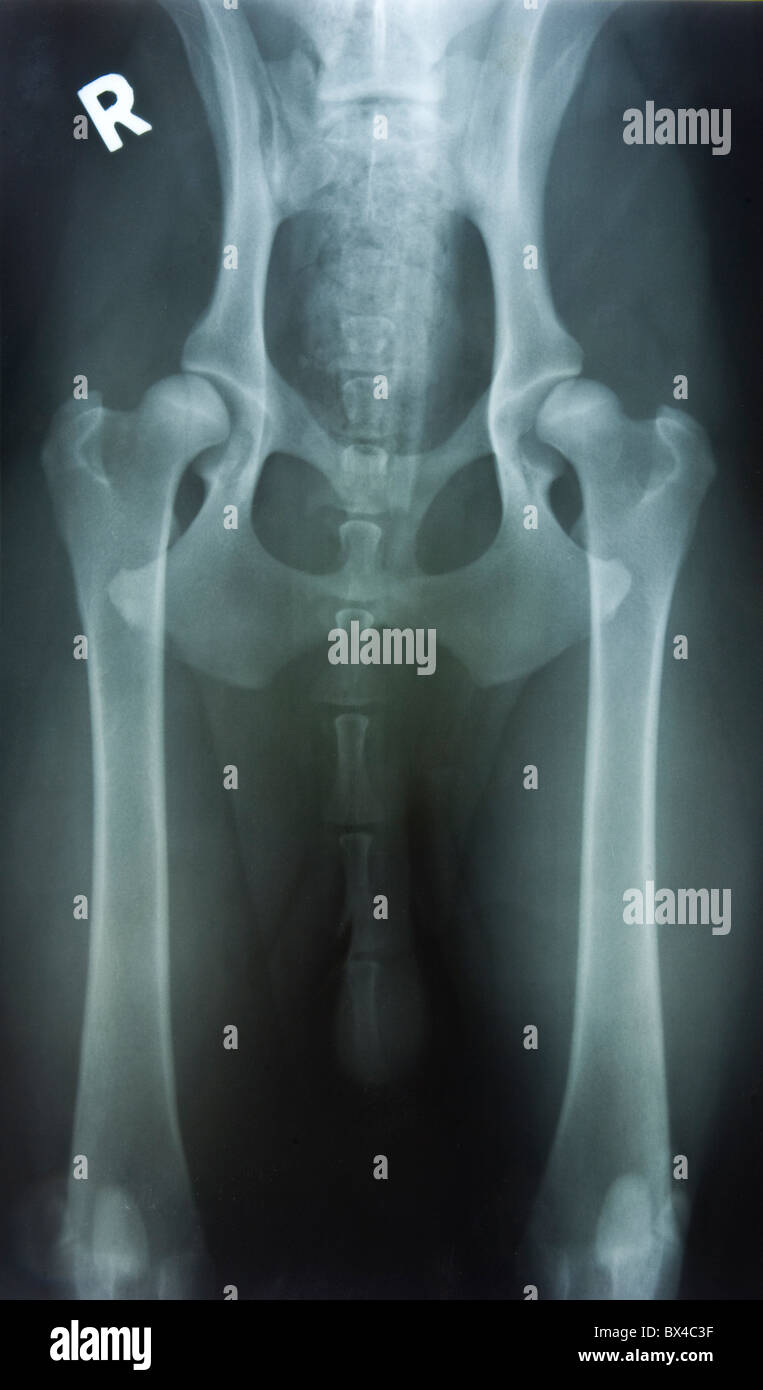

Congenital hip dysplasia. Xray of the hips of a woman with congenital Does Hip Dysplasia Show On X Ray developmental dysplasia of the hip (ddh) is a condition where the ball and socket joint of the hip does not properly form in babies and young children. for imaging assessment of developmental dysplasia of the hip, ultrasound is the modality of choice prior to the ossification of the proximal femoral epiphysis. 4 the acetabulum is most often deficient.. Does Hip Dysplasia Show On X Ray.

Xrays of the hip revealed bilateral femoral head dysplasia. Download